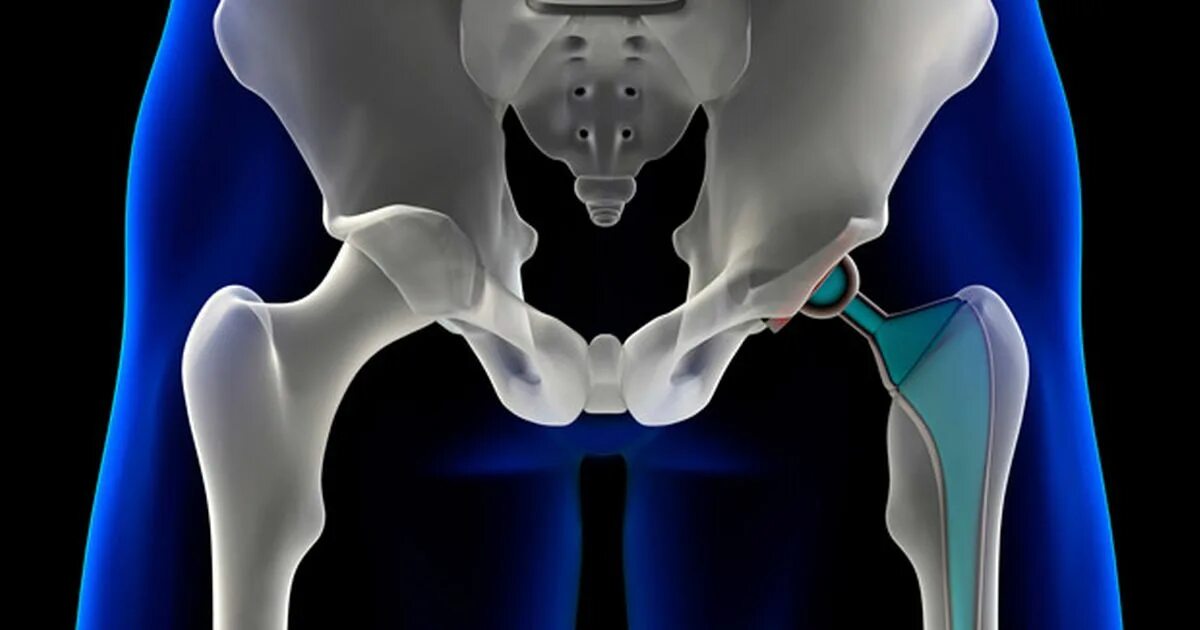

Hip 3. Упражнение хождение на ягодицах. Hip robot joint. Hip 3. Искусственный тазобедренный сустав.

Hip 3. Упражнение хождение на ягодицах. Hip robot joint. Hip 3. Искусственный тазобедренный сустав.

Тазобедренный сустав 3 д. Тазобедренная кость человека. Боль в тазобедренном суставе. Тазобедренный эндопротез райт. Hip 3.

Тазобедренный сустав 3 д. Тазобедренная кость человека. Боль в тазобедренном суставе. Тазобедренный эндопротез райт. Hip 3.

Эндопротезирование тазобедренного сустава операция. Hip 3. Операция эндопротез тазобедренный. Онкологический эндопротез тазобедренного сустава. Тазобедренный сустав 3d.

Эндопротезирование тазобедренного сустава операция. Hip 3. Операция эндопротез тазобедренный. Онкологический эндопротез тазобедренного сустава. Тазобедренный сустав 3d.

Дискомфорт в тазобедренном суставе. Medicad compliant. Hip bone шаблон. Hip 3. Эндопротез зиммер тазобедренного сустава.

Дискомфорт в тазобедренном суставе. Medicad compliant. Hip bone шаблон. Hip 3. Эндопротез зиммер тазобедренного сустава.

Тазобедренный сустав анатомия. Искусственный тазобедренный сустав. Гемиартропластика тазобедренного сустава. Hip 3. Эндопротезирование костей таза рентген.

Тазобедренный сустав анатомия. Искусственный тазобедренный сустав. Гемиартропластика тазобедренного сустава. Hip 3. Эндопротезирование костей таза рентген.

Тазобедренный сустав и бедренная кость. Hip joint. Искусственный тазобедренный сустав. Hips картинки. Hip 3.

Тазобедренный сустав и бедренная кость. Hip joint. Искусственный тазобедренный сустав. Hips картинки. Hip 3.

Болит тазобедренный су тав. Кости таза вертлужная впадина. Зиммер протезы для тазобедренных суставов. Модель кости. Hip 3.

Болит тазобедренный су тав. Кости таза вертлужная впадина. Зиммер протезы для тазобедренных суставов. Модель кости. Hip 3.

Эндопротезирование тазобедренного сустава. Тазобедренный протез. Hip 3. Тазобедренный сустав иконка. Medicad 2d hospital expert.

Эндопротезирование тазобедренного сустава. Тазобедренный протез. Hip 3. Тазобедренный сустав иконка. Medicad 2d hospital expert.

Анатомия вертлужной впадины тазобедренного сустава. Эндопротезирование тазобедренного сустава. Трохантерита тазобедренного сустава. 3hip. Coxa vara тазобедренного сустава.

Анатомия вертлужной впадины тазобедренного сустава. Эндопротезирование тазобедренного сустава. Трохантерита тазобедренного сустава. 3hip. Coxa vara тазобедренного сустава.

Hip 3. Тазобедренный сустав и бедренная кость анатомия. Скелет тазобедренного сустава. Тазобедренный сустав 3d. Hip 3.

Hip 3. Тазобедренный сустав и бедренная кость анатомия. Скелет тазобедренного сустава. Тазобедренный сустав 3d. Hip 3.

Тазобедренный сустав. 3д модель сустава. Hip 3. Hip abduction тренажер. Hip replacement.

Тазобедренный сустав. 3д модель сустава. Hip 3. Hip abduction тренажер. Hip replacement.

Эндопротез тазобедренного сустава. Medicad. Coxa vara тазобедренного сустава. Скелет человека тазобедренный сустав. 3д модель сустава.

Эндопротез тазобедренного сустава. Medicad. Coxa vara тазобедренного сустава. Скелет человека тазобедренный сустав. 3д модель сустава.